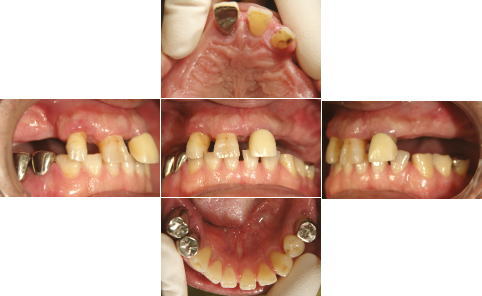

| 治療前 | 治療後 |

| 上顎、下顎共にグラツキの著しい歯は抜歯し、上顎はAll-on-4、下顎奥歯は通常のインプラントブリッジとしました。 | |